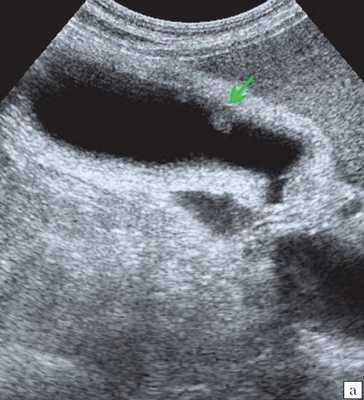

При УЗИ брюшной полости: расширены внутрипеченочные протоки (сегментарные до 6 мм, долевые до 10 мм). ОЖП 14-15 мм. Желчный пузырь 120 30 мм, стенка 3 мм, конкрементов не выявлено. ПЖ нормальных размеров, контуры ровные, четкие. Структура диффузно неоднородная, повышенной эхогенности. Панкреатический проток расширен до 5 мм. Заключение: ультразвуковая картина низкого печеночного блока с билиарной гипертензией, блок на уровне БДС, терминального отдела ОЖП (рис. 7).

а) Увеличенный желчный пузырь с густой взвесью внутри (красная стрелка) и расширенный ОЖП (синяя стрелка).

в) Расширение панкреатического протока (зеленая стрелка).